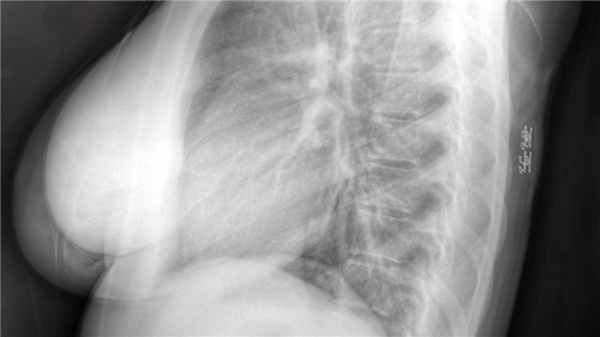

Липома - диагностика, методы лечения

Доброкачественные новообразования, развивающиеся в жировой ткани, прежде всего, кожи, но бывают липомы молочной железы, головного и спинного мозга. Опухоли растут медленно и редко малигнизируются.

- липомы грудной клетки – образованием затронуты легкие

Липома головного и спинного мозга

Липомы позвоночника составляют 35% всех новообразований спинного мозга, чаще встречаются у девочек.

- липома спинного мозга (интрадуральная) встречается редко и составляет 4% от всех липом. Чаще ее выявляют в грудном отделе позвоночника у детей, патологии костей или кожи при ней не бывает. Если вырастает до больших размеров, то проявляет себя симптомами сдавления спинного мозга. Это одно из самых малоизученных новообразований.